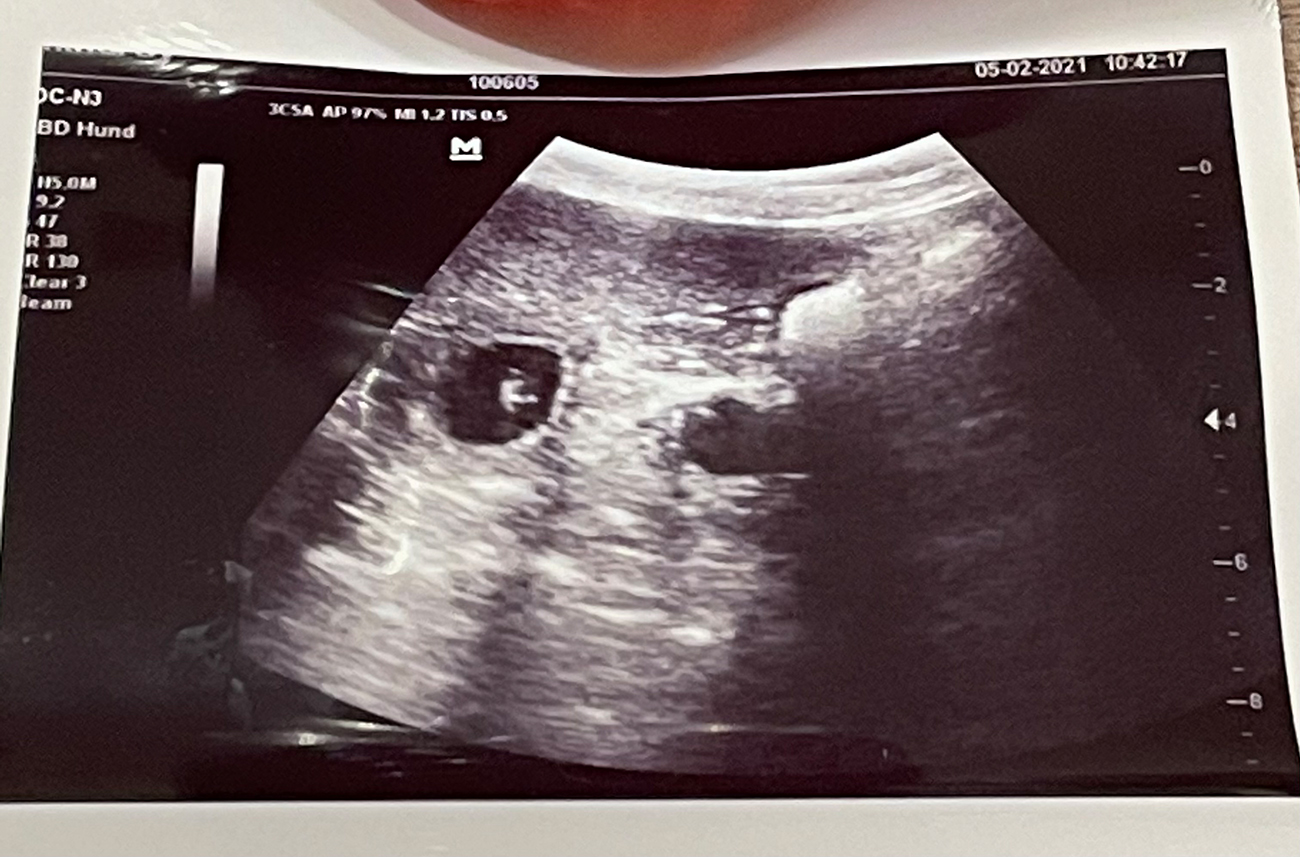

Heute war also der Tag der Tage. Der Tag an dem man Gewissheit bekommt, ob die Hündin aufgenommen hat oder nicht.

Auch wenn in den letzten Tagen einiges für eine Trächtigkeit gesprochen hat, so wollten wir es gerne

von unserer Tierärztin absegnen lassen.

Beim Ultraschall wurden auf Anhieb einige Fruchtanlagen gesichtet. Die genaue Anzahl wollte ich aber nicht wissen.... ein bisschen Spannung soll uns und den Welpeninteressenten schon noch in den kommenden Wochen erhalten bleiben.  |

Wir freuen uns einfach riesig darüber, dass bald kleine K-Racker den Bagalutenhof besetzen werden.